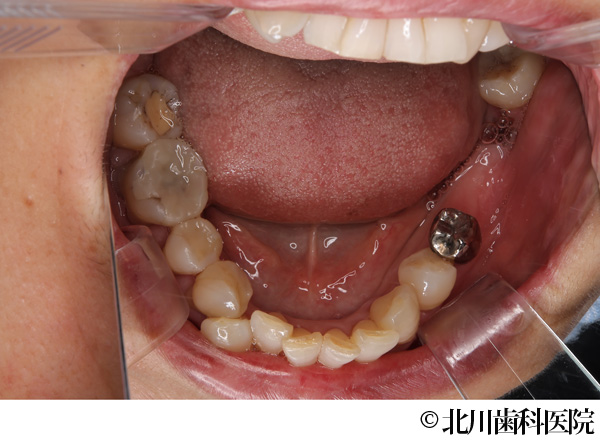

【症例1】インプラントと自家歯牙移植にて機能回復を行った症例

- 治療前

- インプラントと自家歯牙移植にて機能回復を行った症例

- 737,000円(税込)

- 1年3ヵ月

- 女性・50代

左下の奥歯が腫れて痛みがあり、抜歯後にインプラントを希望されて来院されました。

左下の奥歯は2本分の歯を喪失することになるため、抜歯する予定の歯の一つ手前にインプラントを埋め込み、抜歯部には親知らずを移植しクラウン(被せ物)を装着することで対応しました。

インプラントと移植歯により喪失した歯を補うことができ、審美面・機能面の回復につながりました。また、インプラント埋入と同時に移植を行うことで手術が一度に終わり身体の負担を軽減して行うことができました。